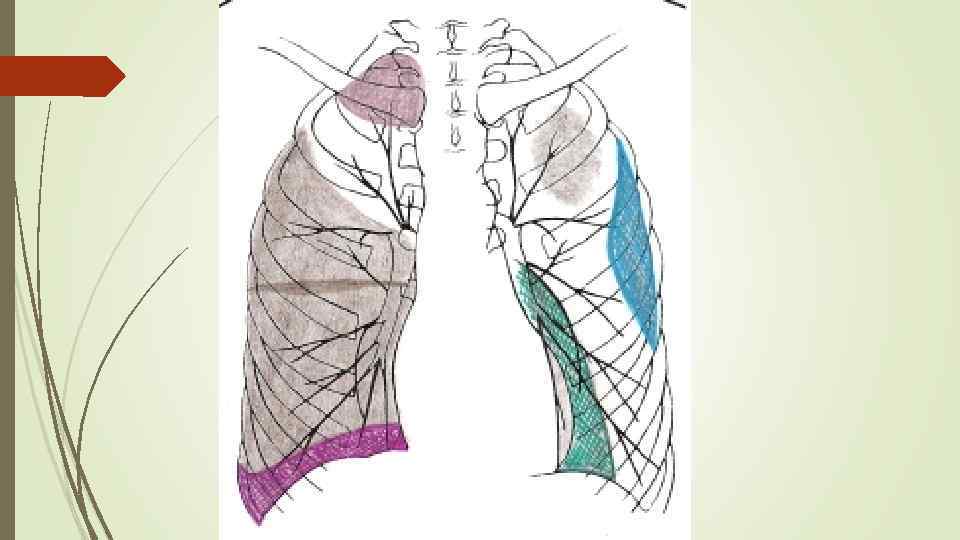

Осумкованные плевриты: а) пристеночные (паракостальные) осумкования, прилежащие широким основанием к поверхности ребер; б) верхушечные (апикальные) осумкования; в) диафрагмальные (базальные) осумкования, расположенные между основанием легкого и диафрагмой; г) междолевые (интерлобарные) осумкования, расположеные между долями легких; д) парамедиастинальные осумкования, расположенные в заворотах парамедиастинальной плевры.

Осумкованные плевриты: а) пристеночные (паракостальные) осумкования, прилежащие широким основанием к поверхности ребер; б) верхушечные (апикальные) осумкования; в) диафрагмальные (базальные) осумкования, расположенные между основанием легкого и диафрагмой; г) междолевые (интерлобарные) осумкования, расположеные между долями легких; д) парамедиастинальные осумкования, расположенные в заворотах парамедиастинальной плевры.